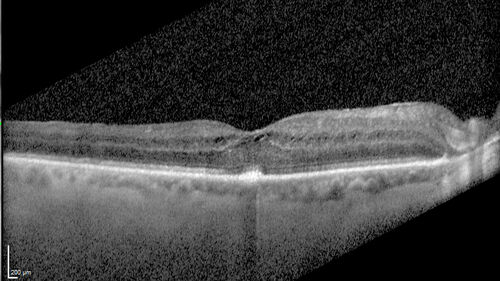

Paclitaxel induced cystoid macular edema - reversed when chemo stopped

74 year old retired physician  About 2-3 weeks ago there was gradual vision loss in the right eye. The patient was seen by an ophthalmologist who saw macular swelling and injected vabysmo. He has been on chemotherapy (Carbiplatin and Carboxytaxol for 2 cancers - advanced prostrate diagnosed 2019 - has had brain surgery AND squamous lung cancers treated with radiation)

Medical Hx: Prostate cancer (Onset: 2018). Pulmonary and bone cancer metastatic. Brain cancer metastasized from prostate cancer.

Surgical Hx: Right frontal & Frontoparietal Craniotomy (Onset: 2024). Appendectomy. Hemorrhoidectomy. Herniorrhaphy. Prostate. Systemic Meds: Chemotherapy. Radiation. Eligard Every 3 Months 22.5 MG per 0.375 ML Prefilled Syringe. MIRALAX prn. Tums Freshers 500 MG Chewable Tablet. Vitamin D. XGEVA.

VA OD: Dcc20/125+1

VA OS: Dcc20/125-2

TP: OD:12 OS:15